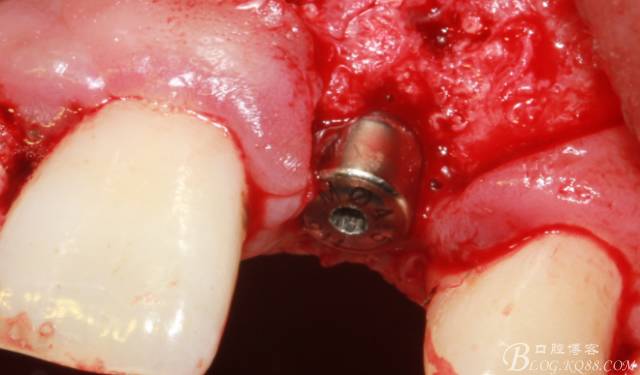

取出影響種植入路的長(zhǎng)鈦釘。

擴(kuò)孔。

骨擠壓

植入植體